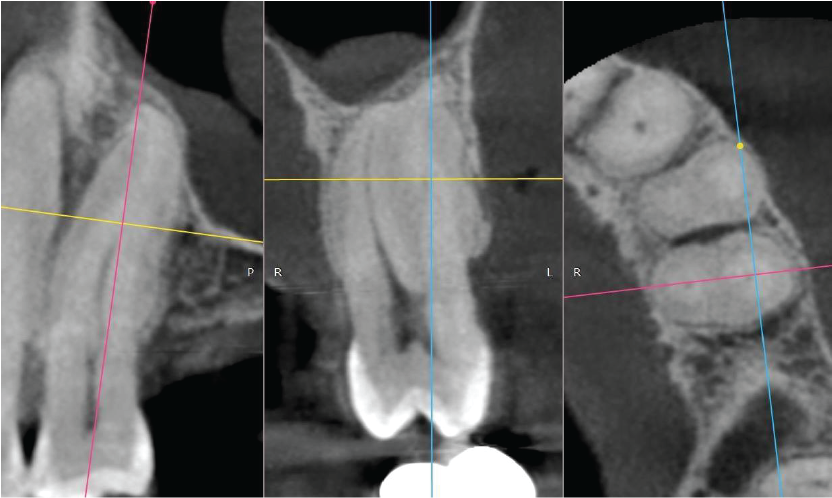

The UL5 has two roots which are practically fused due to hypercementosis. The apical half of the buccal root is not visible (possibly obliterated). Image 3

Between the UL4 and UL5 there is a well-defined radiolucency measuring approximately 6mm diameter. The lesion envelops the UL4 apex and abuts the apical half of the UL5 root. The genesis of the radiolucency is not of obvious endodontic origin since both teeth are unrestored and the location is not typically centred around the apex. If the teeth are vital, suggested tentative diagnosis are odontogenic cyst such as lateral periodontal cyst or fibro-osseous origin. Image 4